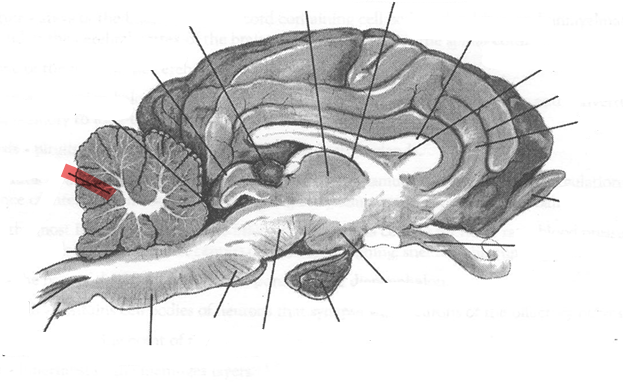

Nervous system labelling

Identify highlighted arrow

Spinal cord

2

New cards

Identify highlighted arrow

Medulla

3

New cards

Identify highlighted arrow

Pons

4

New cards

Identify highlighted arrow

Midbrain

5

New cards

Identify highlighted arrow

Hypophysis

6

New cards

Identify highlighted arrow

Hypothalamus

7

New cards

Identify highlighted arrow

Optic nerve

8

New cards

Identify highlighted arrow

Olfactory bulb

9

New cards

Identify highlighted arrow

Gyrus

10

New cards

Identify highlighted arrow

Sulcus

11

New cards

Identify highlighted arrow

Corpus callosum

12

New cards

Identify highlighted arrow

Third ventricle

13

New cards

Identify highlighted arrow

Thalamus

14

New cards

Identify highlighted arrow

Pineal body

15

New cards

Identify highlighted arrow

cerebellum

16

New cards

Identify highlighted arrow

Fourth ventricle